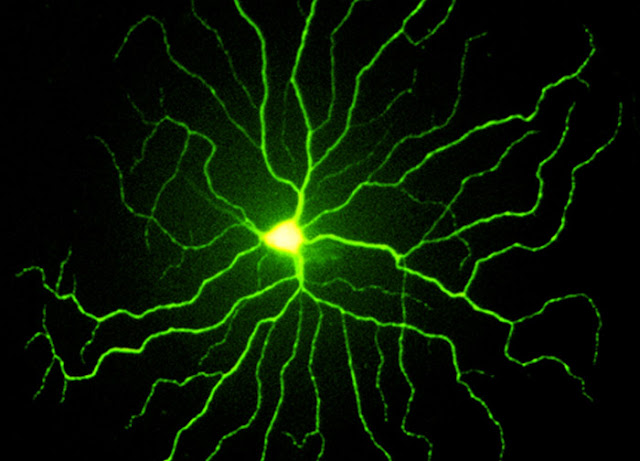

Rabbit Retina 兔子視網膜

Dr. Peter Koulen

Forth Worth, TX, USA

Specimen: Rabbit Retina

Technique: Confocal